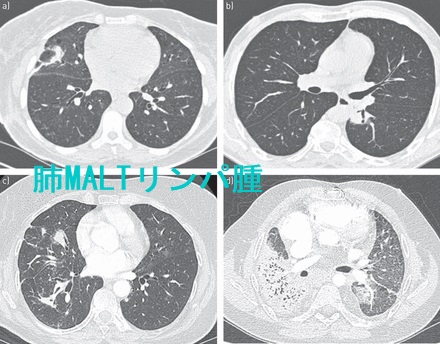

肺原発悪性リンパ腫は、肺悪性腫瘍の1%に過ぎません。MALTリンパ腫は、肺原発悪性リンパ腫の約90%を占めます。肺MALTリンパ腫はほとんど原発性で、他臓器MALTリンパ腫の肺転移は非常にまれです。

肺原発悪性リンパ腫は、気道のリンパ組織から発生し、肺CTではコンソリデーション(血管や気管支壁の不明瞭化)・腫瘤状陰影と、その辺縁部の粒状影・すりガラス陰影、胸膜に沿った粒状影を認めます。